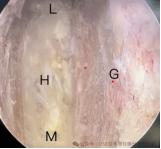

4.微创脊柱内镜技术:PELD+UBE+OSE

脊柱内镜技术是一项开展较早的脊柱外科微创技术,与传统开放手术相比,它是借助天然解剖间隙建立微创工作通道,解除神经压迫;对椎旁肌肉损伤较小,且能够最大程度地保留完整的脊柱结构,维持了术后脊柱的稳定,具有创伤小、出血少、恢复快、并发症少、疗效确切等优点。目前已开展椎间孔镜下髓核摘除术,单侧双通道脊柱内镜(UBE)下椎管减压术并处于区域内领先水平。好看视频下载

在江苏省内率先开展了单孔分体式脊柱内镜技术(OSE),处国内领先水平。

单孔孔镜

单侧双通道技术

单孔分体式内镜下腰椎固定融合技术